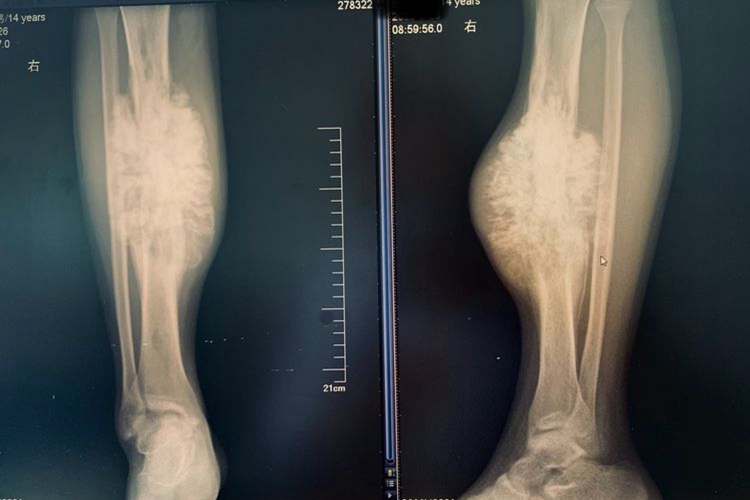

骨癌患者的骨头可出现骨质破坏的情况,肿瘤浸润骨组织及周围组织,可见团块状的瘤骨和钙化。骨癌患者的骨头变化一般不能直观见到,多是通过影像学检查或手术切除的方式观察。